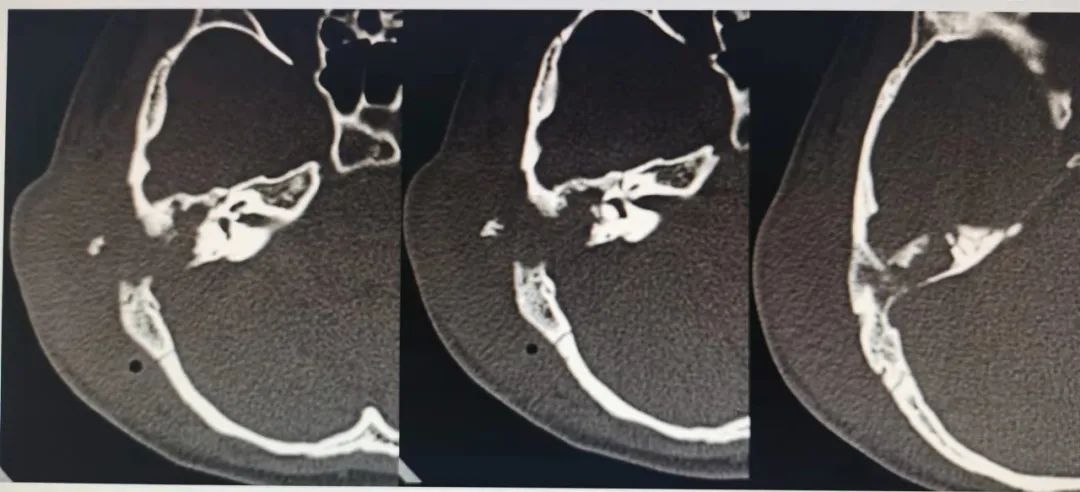

「从耳内镜及 CT 片看,患儿目前考虑为中耳胆脂瘤,病变已侵蚀乳突骨质致耳后脓肿、乙状窦暴露、脑膜暴露,同时侵蚀致听小骨破坏致听骨链中断,在彻底清除病灶的同时最好能重建听力。」

在与家长充分沟通后,小库尔班被收治进耳鼻咽喉科,并给予耳后伤口换药、引流及静脉滴注抗生素等基础治疗。「小小的胆脂瘤看似不起眼,但结合影像学检查发现,它的病变范围正在扩大,一场手术治疗势在必行。」钟晓声副主任医师,立即联合耳鼻咽喉科米尔班祖农主任、林勇副主任和全体医生以及影像中心、手术室、麻醉科的专家进行会诊。